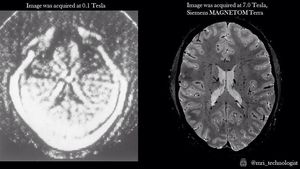

First ever human brain MR image, acquired at 0.1 Tesla (Courtesy of Ian Young), and nowadays ultra-high resolution SWI, acquired at 7 Tesla!